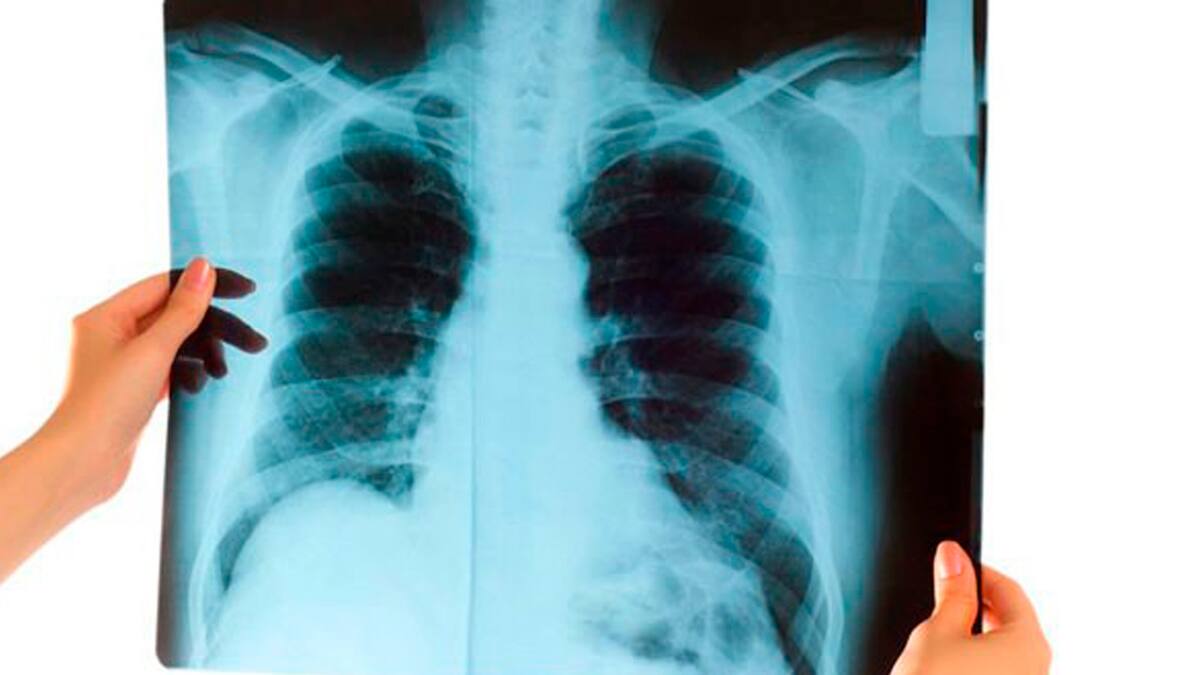

En Colombia las cifras también son representativas, de acuerdo el Ministerio de Salud y Protección Social, 34.800 personas mueren anualmente por enfermedades asociadas al consumo del tabaco, 3.076 son causadas por los cánceres de tráquea, bronquios y pulmón, y en mayor prevalencia 4.584 muertes son causadas por las enfermedades crónicas de las vías respiratorias, entre ellas la enfermedad pulmonar obstructiva crónica (EPOC).